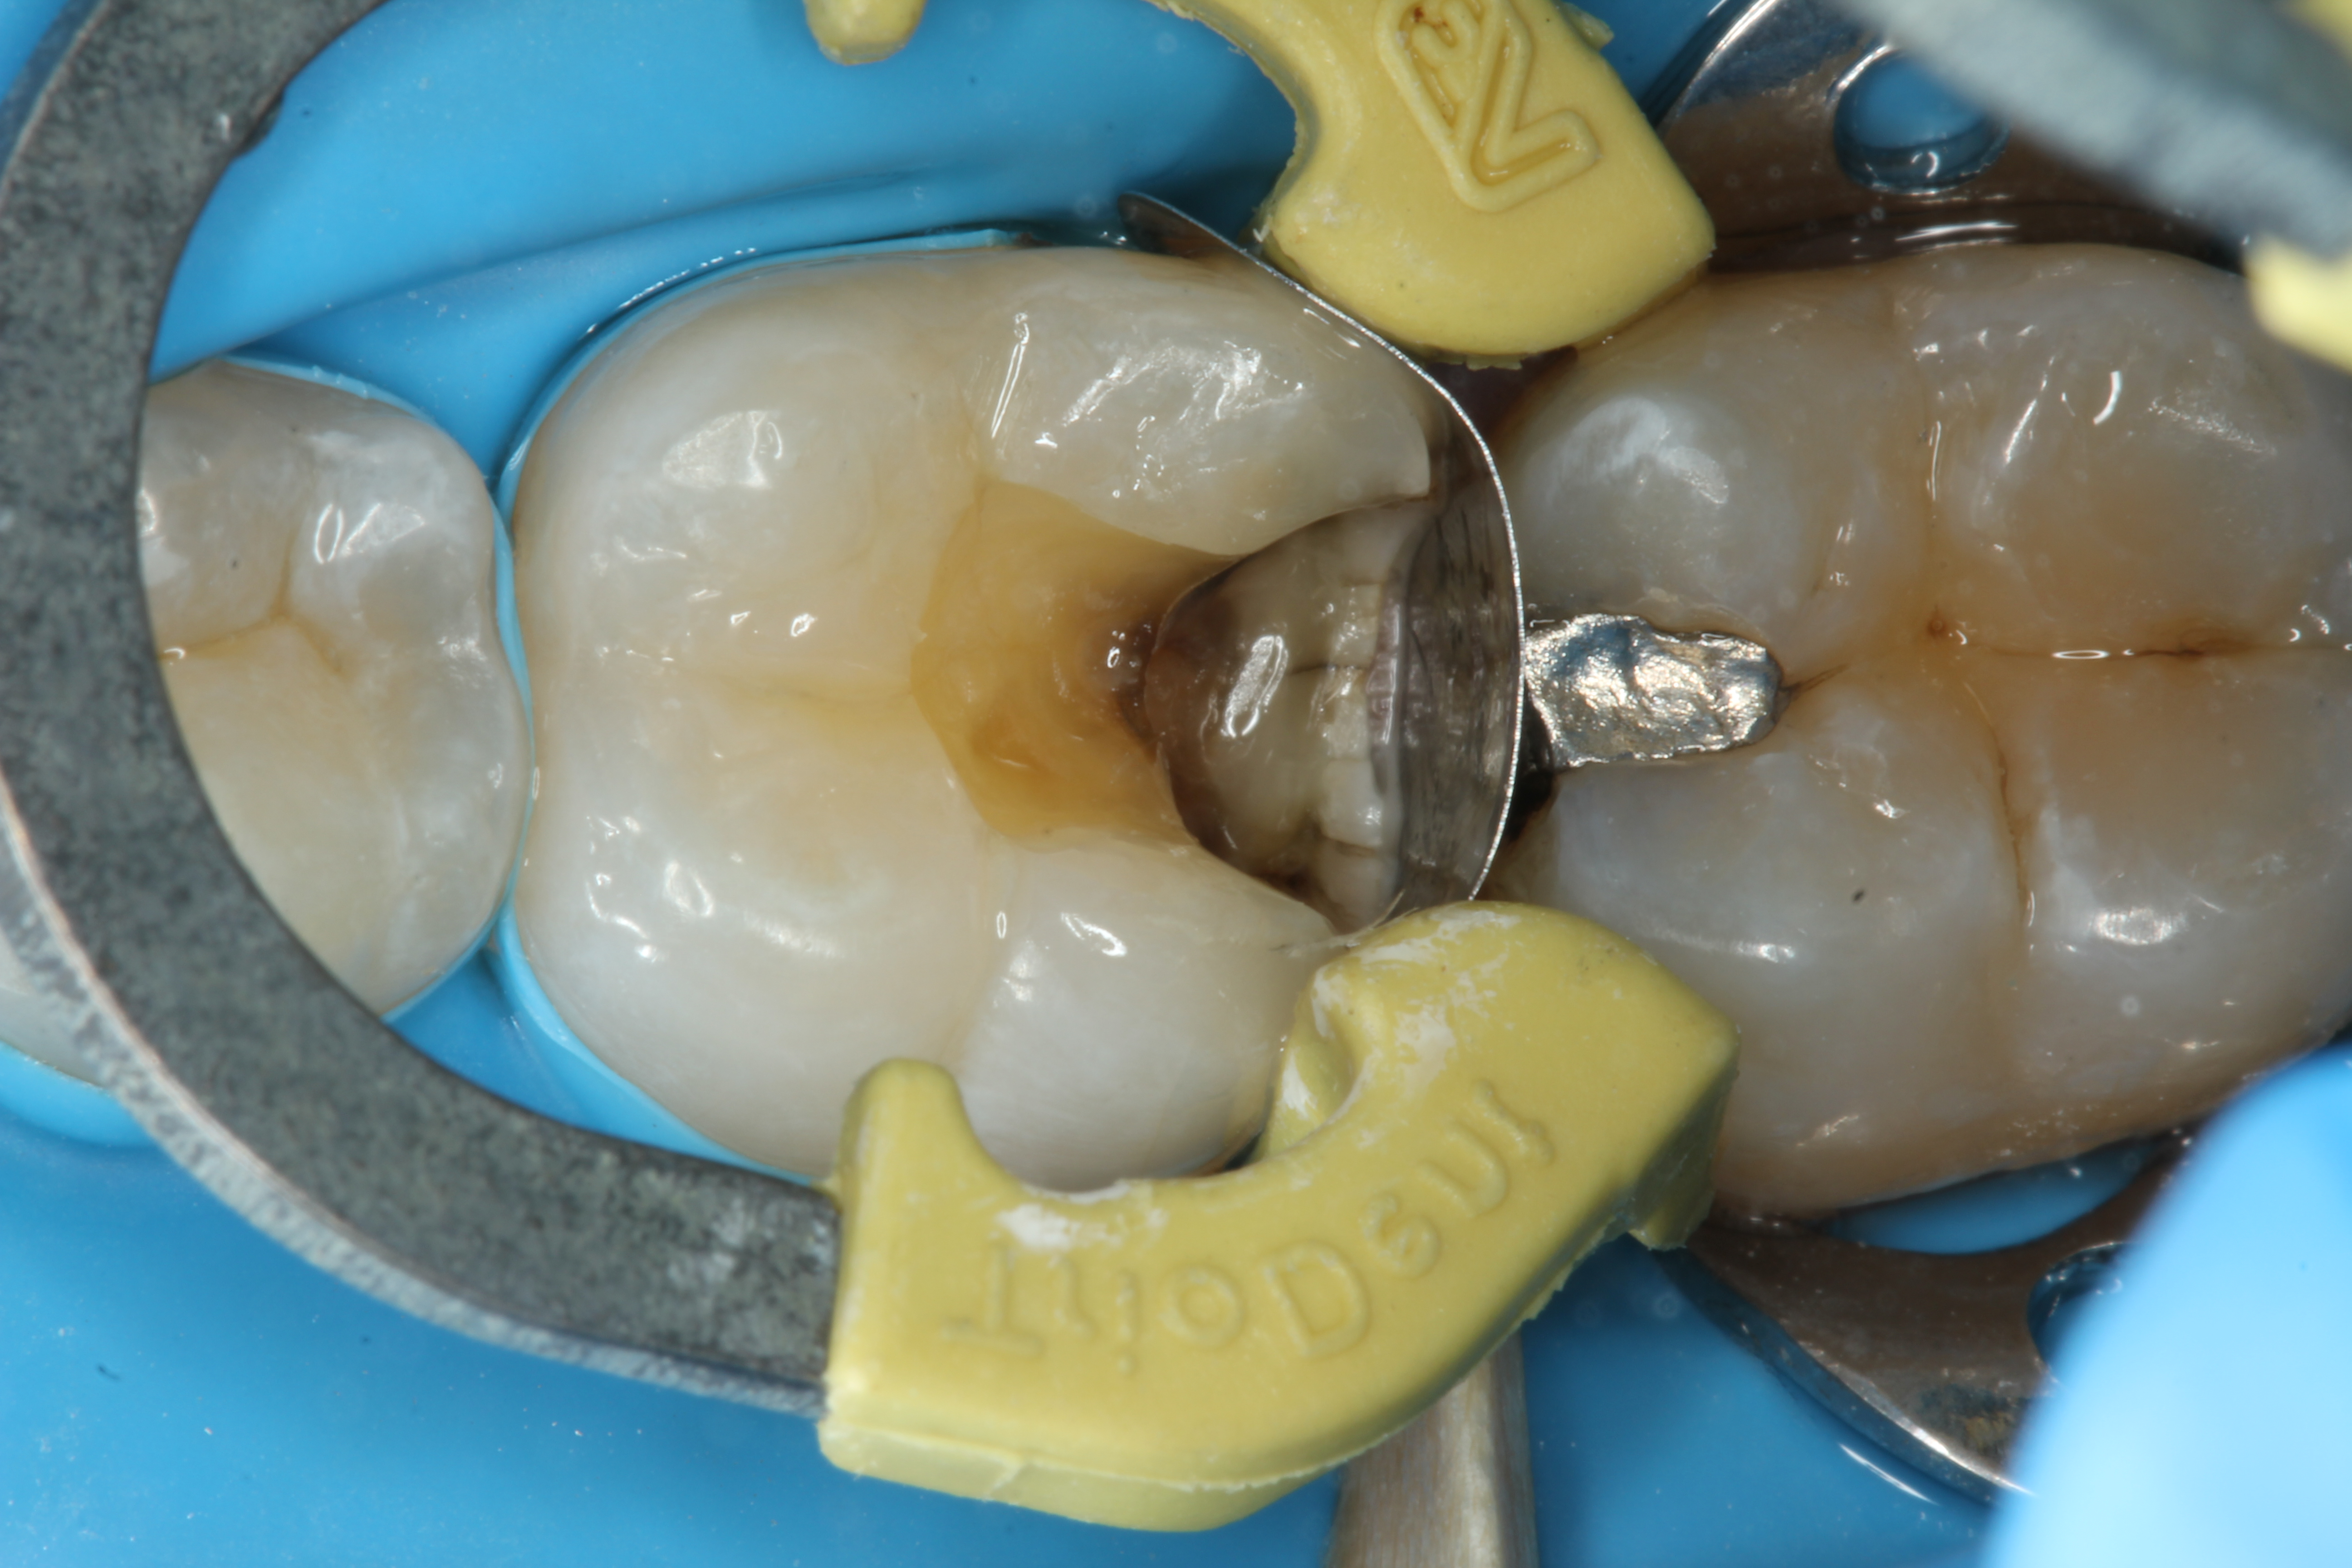

To determine how much to remove, it is important to understand the difference between infected dentin and affected dentin. The infected layer of dentin is highly demineralized, is physiologically unable to remineralize, and contains irreversibly denatured collagen fibrils with a virtual disappearance of cross-linkages.18 It contains bacteria and degraded collagen that cannot be remineralized. On the other hand, the affected dentin has a minimal concentration of bacteria, and the collagen network is still viable.19 Clinically, affected and infected dentin are differentiated by their hardness. Infected dentin is soft and can be easily removed with a spoon excavator (Figure 4). Affected dentin is leathery and requires firm pressure to be removed with a spoon excavator (Figure 5).20

Fig 4. Removing soft infected dentin.

Figure 4

Fig 5. Removing firm affected dentin.

Figure 5